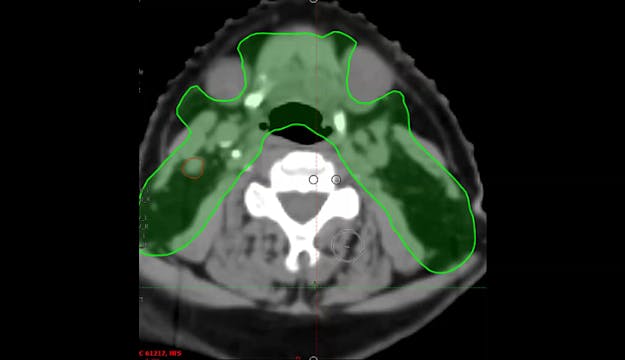

04/29/2024 - Dr. David Sher - Radiation Oncology - Head & Neck

Chartrounds US - Head and Neck Cancer